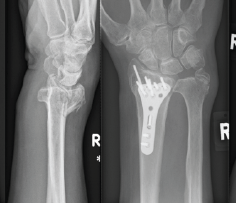

Comparative Analysis of Dorsal Distraction Plating Versus External Fixation in the Management of Intra-Articular Distal Radius Fractures

Ismail Pandor , Abhishek Sharma , Paresh Patil , Sushant Pandit , Prathamesh Karad , Alim Shaikh

Modified Minimally Invasive Reduction and Osteosynthesis System Technique for Fixation of Distal Radius

Atanu Mohanty , Anuraag Mohanty , Jitendra Sarangi , Sibananda Ratha , Rabindra Kumar Nayak